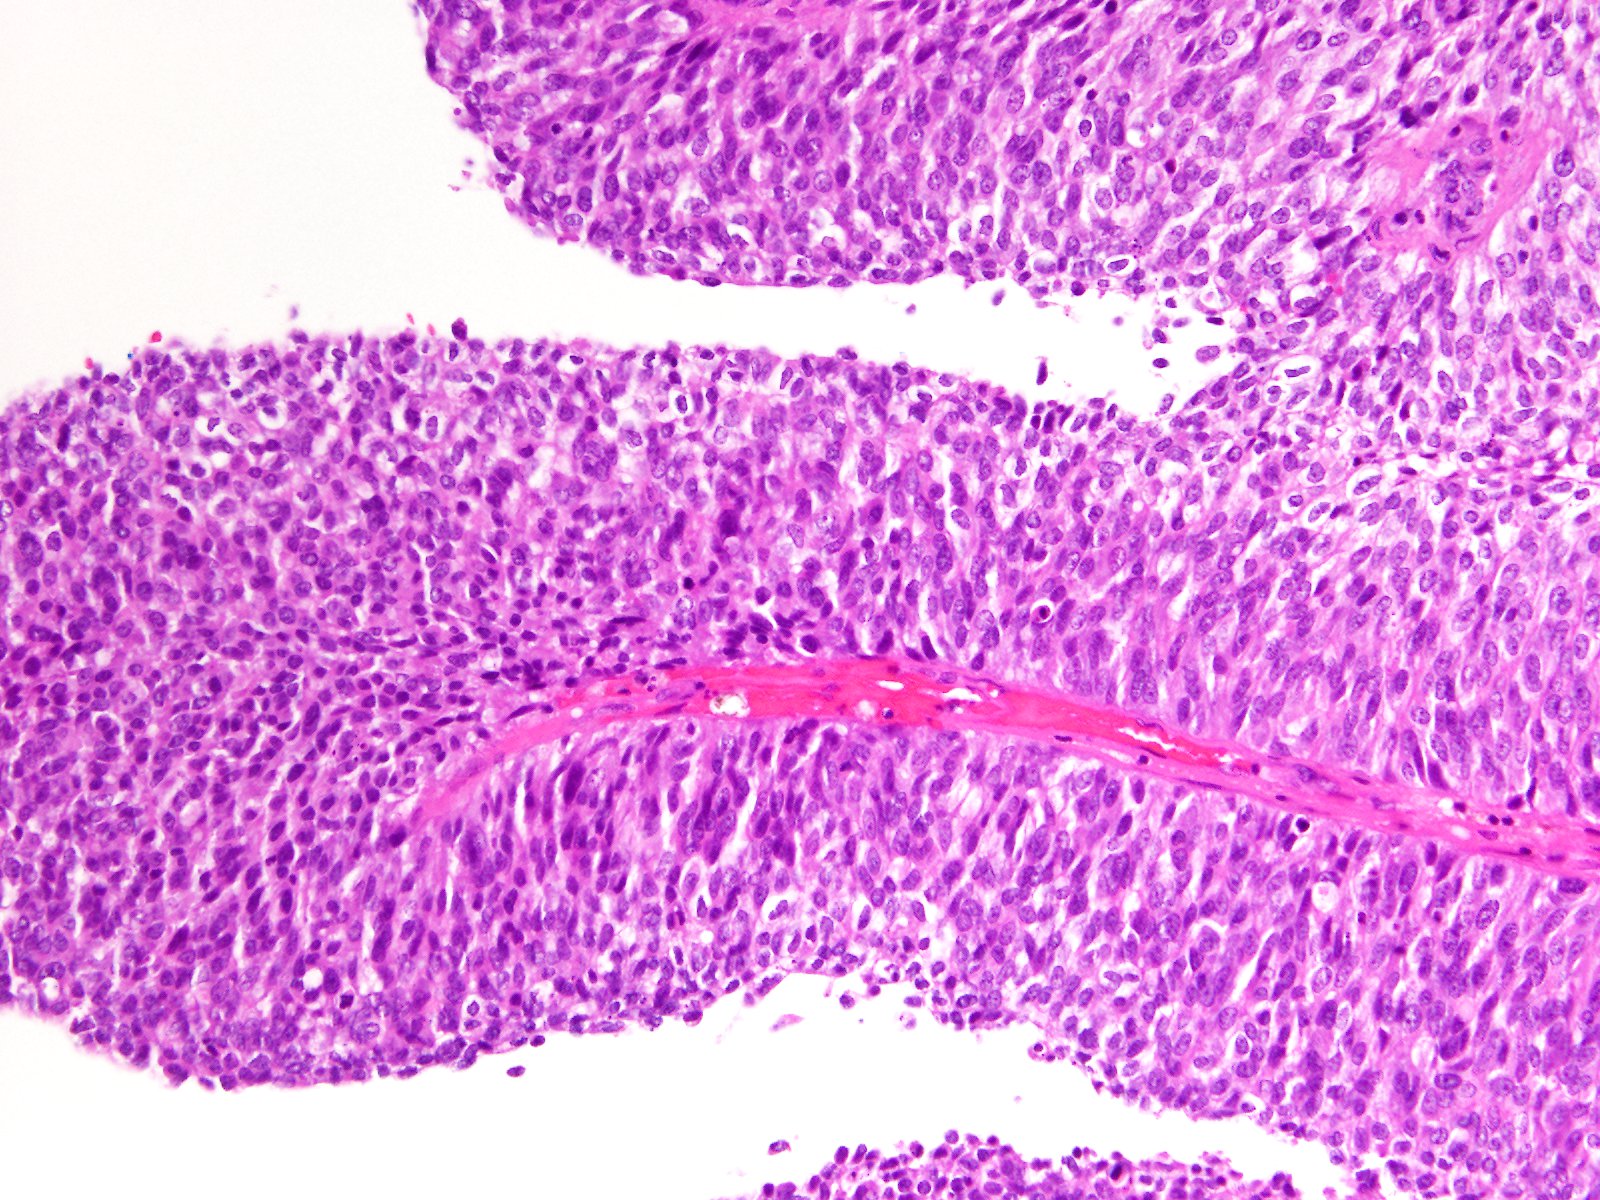

Consensus grade: High-grade papillary urothelial carcinoma (HG-PUC)

Case description (by case creator):

Papillary tumor in TUR-BT.